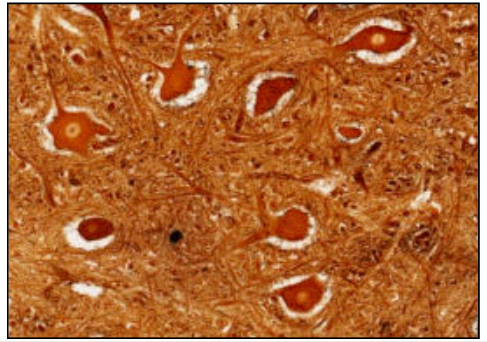

SILVER STAIN - NEURONS

• neurons are large

• 25-60 microns

• because of slide thickness you cannot see all processes

• 1-5 dendritic processes

• metabolically active

• fully differentiated

NERVE CELL BODIES (SILVER) * either @ CNS or in discrete ganglia close to spinal cord * exception is PNS with clusters close to organ innervated * silver stain has affinity for cytoskeleton of cells * neurons have **developed cytoskeleton,** therefore stain heavily GOLDEN BROWN - nucleus pale but nucleolus black **cytoskeleton - mictrotubules** (tubulin and dynein) = axonal transport i.e. vesicles from golgi to end and back/**neurofilaments** (intermediate architecture) = axonal diameter **no. processes** unipolar - sensory bipolar - interneurons multipolar - motor neurons